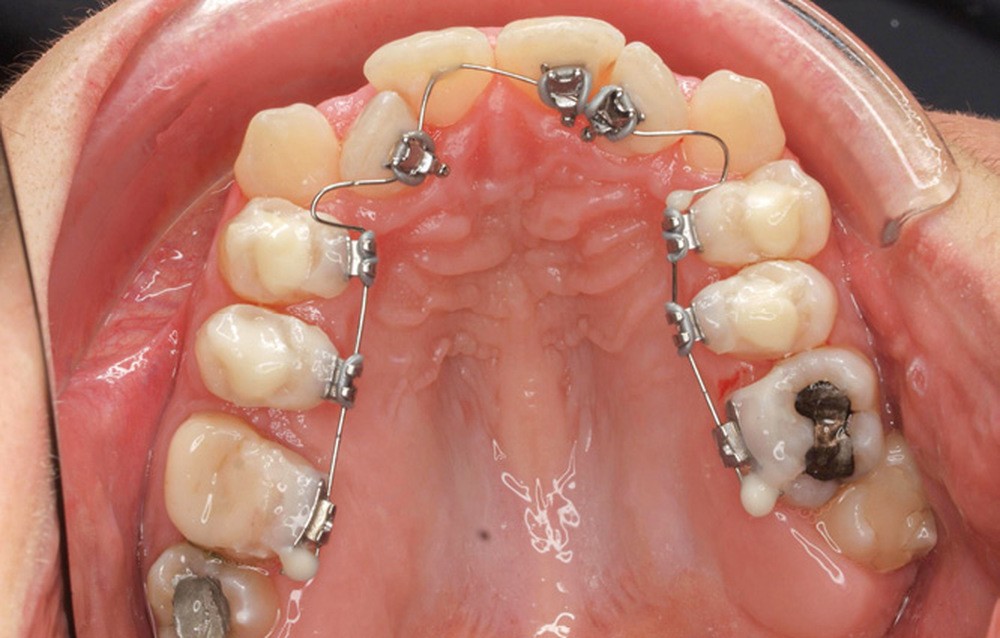

- Quatrième rendez-vous (fig. 2d) : des arcs TMA .017 x .017 sont posés. Les premières et deuxièmes molaires sont collées en vestibulaire avec un arc sectionnel NiTi 0,019×0,025.

- Cinquième rendez-vous (fig. 2e) : des arcs TMA .017 x .025 sont posés et des tubes linguaux collés sur 17 et 27 pour le port d’élastiques criss-cross nocturnes.

- Sixième rendez-vous (fig. 2f) : les cales sont déposées. Un pliage de finition sur 21 est réalisé pour améliorer son angulation.

- Septième rendez-vous : les appareils sont déposés. Une empreinte numérique est prise pour réaliser trois aligneurs afin de parfaire le résultat occlusal et esthétique (fig. 3a-h).